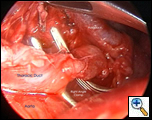

Exploration of this area bluntly will reveal the thoracic duct as a thin tubular structure with occasional peristalsis (Video 5). Once a sufficient length of duct is isolated it is doubly clipped using 5 or 10mm clips depending on the size of the duct and is divided (Figures 4-6). Transection with a linear cutting stapler with a vascular load (30mm length, 2.0mm staple height) works just as well (Video 6). The stapler or clip applier can be introduced through the working incision or the incision used for retraction of the diaphragm. If an adequate length of the duct can be isolated, a portion can be excised and sent for frozen section to confirm its identity.

| Figure 4: Thoracic Duct isolation. | Figure 5: Thoracic Duct Ligation. | Figure 6: Thoracic Duct Divided. |